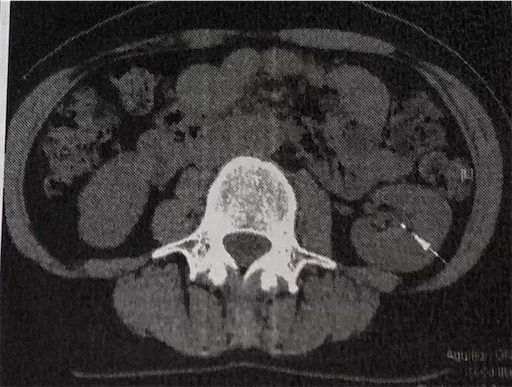

こちらがそのときに撮ったCT画像の1枚です。

気になったのは、背骨の歪み具合・・・

めっちゃ歪んでる。

採尿やCT検査の結果、石ころが腎臓にありました。

ただ、尿管結石だと言われたのに、尿管にはやつは見当たらなかったんです。